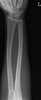

Lucent bone lesion with sclerotic rim

May Be Caused by